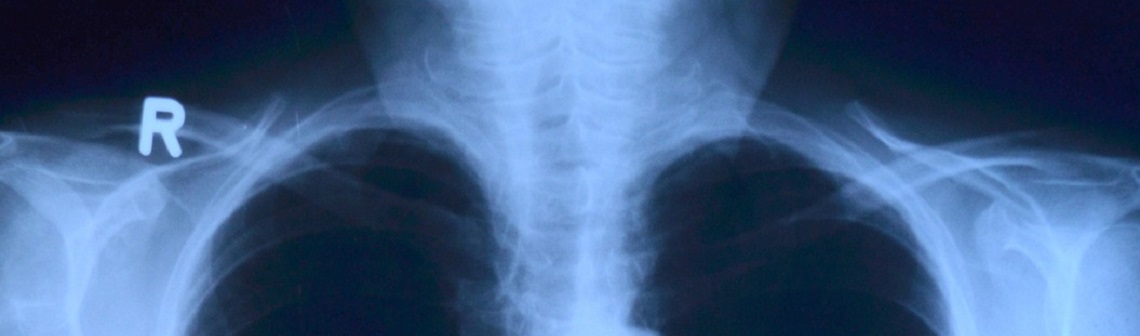

De nos jours, le travail des radiologues se densifie, malgré certains algorithmes de reconnaissance vocale qui allègent déjà un peu le travail. Mais avec l’augmentation de la rapidité de l’imagerie médicale, les médecins sont contraints d’étudier plus de dossiers par heure qu’auparavant. Les fondateurs de Raidium veulent résoudre ce problème en accélérant le temps d’analyse des radiologues grâce à des modèles d’IA. Il s’agirait ainsi de générer directement le bilan radiologique ou de détecter des anomalies sur les images, toujours sous le contrôle du médecin. De plus, avec cette compression du temps, les radiologues n’ont pas la possibilité d’étudier certains éléments comme la taille des organes et des tumeurs. La quantité de données à examiner est énorme, de même que la charge mentale des spécialistes.

Après avoir récolté des milliers de données auprès de différents hôpitaux, les cofondateurs vont maintenant proposer un modèle de leur produit, afin de montrer sa polyvalence. Raidium a déjà un partenariat avec les hôpitaux parisiens pour s’attaquer aux maladies du foie comme l’hypertension portale (complication majeure de la cirrhose) ou la Nash (stéatohépatite non alcoolique également nommée « maladie du foie gras »). Ces pathologies sont mal diagnostiquées et donc mal soignées. Le produit développé par la start-up pourrait aussi être utile dans le diagnostic de certains cancers. Quand la maladie se métastase, les analyses sont compliquées, car l’évolution des tumeurs dans les différents organes doit être étudiée, chose que les IA actuelles ne sont pas aujourd’hui capables de faire. L’IA proposée par Raidium pourra servir afin de réaliser des biopsies virtuelles pour la Nash, prédire de façon non invasive des marqueurs invasifs ou encore mieux évaluer le volume tumoral dans le cadre d’essais cliniques.